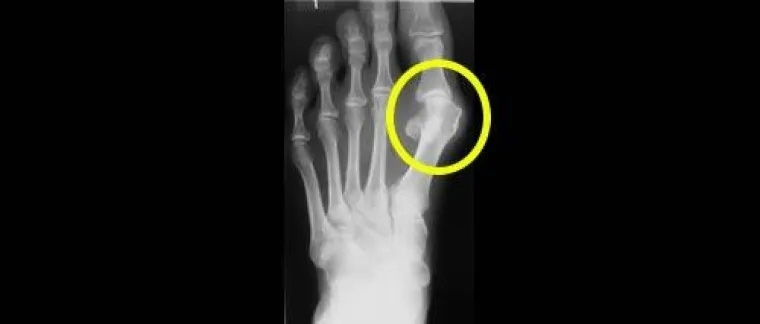

Fehlstellungen der Großzehe können zu erheblichen Beschwerden führen. In ausgeprägten Fällen können handelsübliche Schuhe nicht mehr getragen werden. Eine Fehlstellung der Großzehe nimmt über die Jahre langsam zu. Dieser Prozess kann leider durch keine nicht-operative Therapie umgekehrt werden. Möglicherweise helfen Einlagen, das Fortschreiten der Erkrankung zu verlangsamen. Aufhalten können Einlagen die Entwicklung eines Hallux valgus jedoch nur in sehr frühen Stadien.

"Eine Zehenfehlstellung führt zu einer anormalen Belastung des Gelenks, was langfristig einen vorzeitigen Gelenkverschleiß begünstigt. Ist eine Arthrose erst einmal entstanden, ist die Bewegung der Großzehe nur noch unter Schmerzen möglich," weiß Dr. Jan-Hauke Jens vom Zentrum für Endoprothetik in Hamburg. "Leider denken aber immer noch viele Patienten, mit Einlagen oder breitem Schuhwerk könne geholfen werden," so Jens. Für alle Interessierten bieten die Chefärzte des Zentrum für Endoprothetik der Hamburger Schön Klinik daher ein GesundheitsGespräch an; "Fußorthopädie - Neue Trends 2010" heißt es und findet statt am 23. Juni 2010 um 18.00 Uhr. Eine Anmeldung ist unter (040) 20 92 - 73 00 erforderlich.